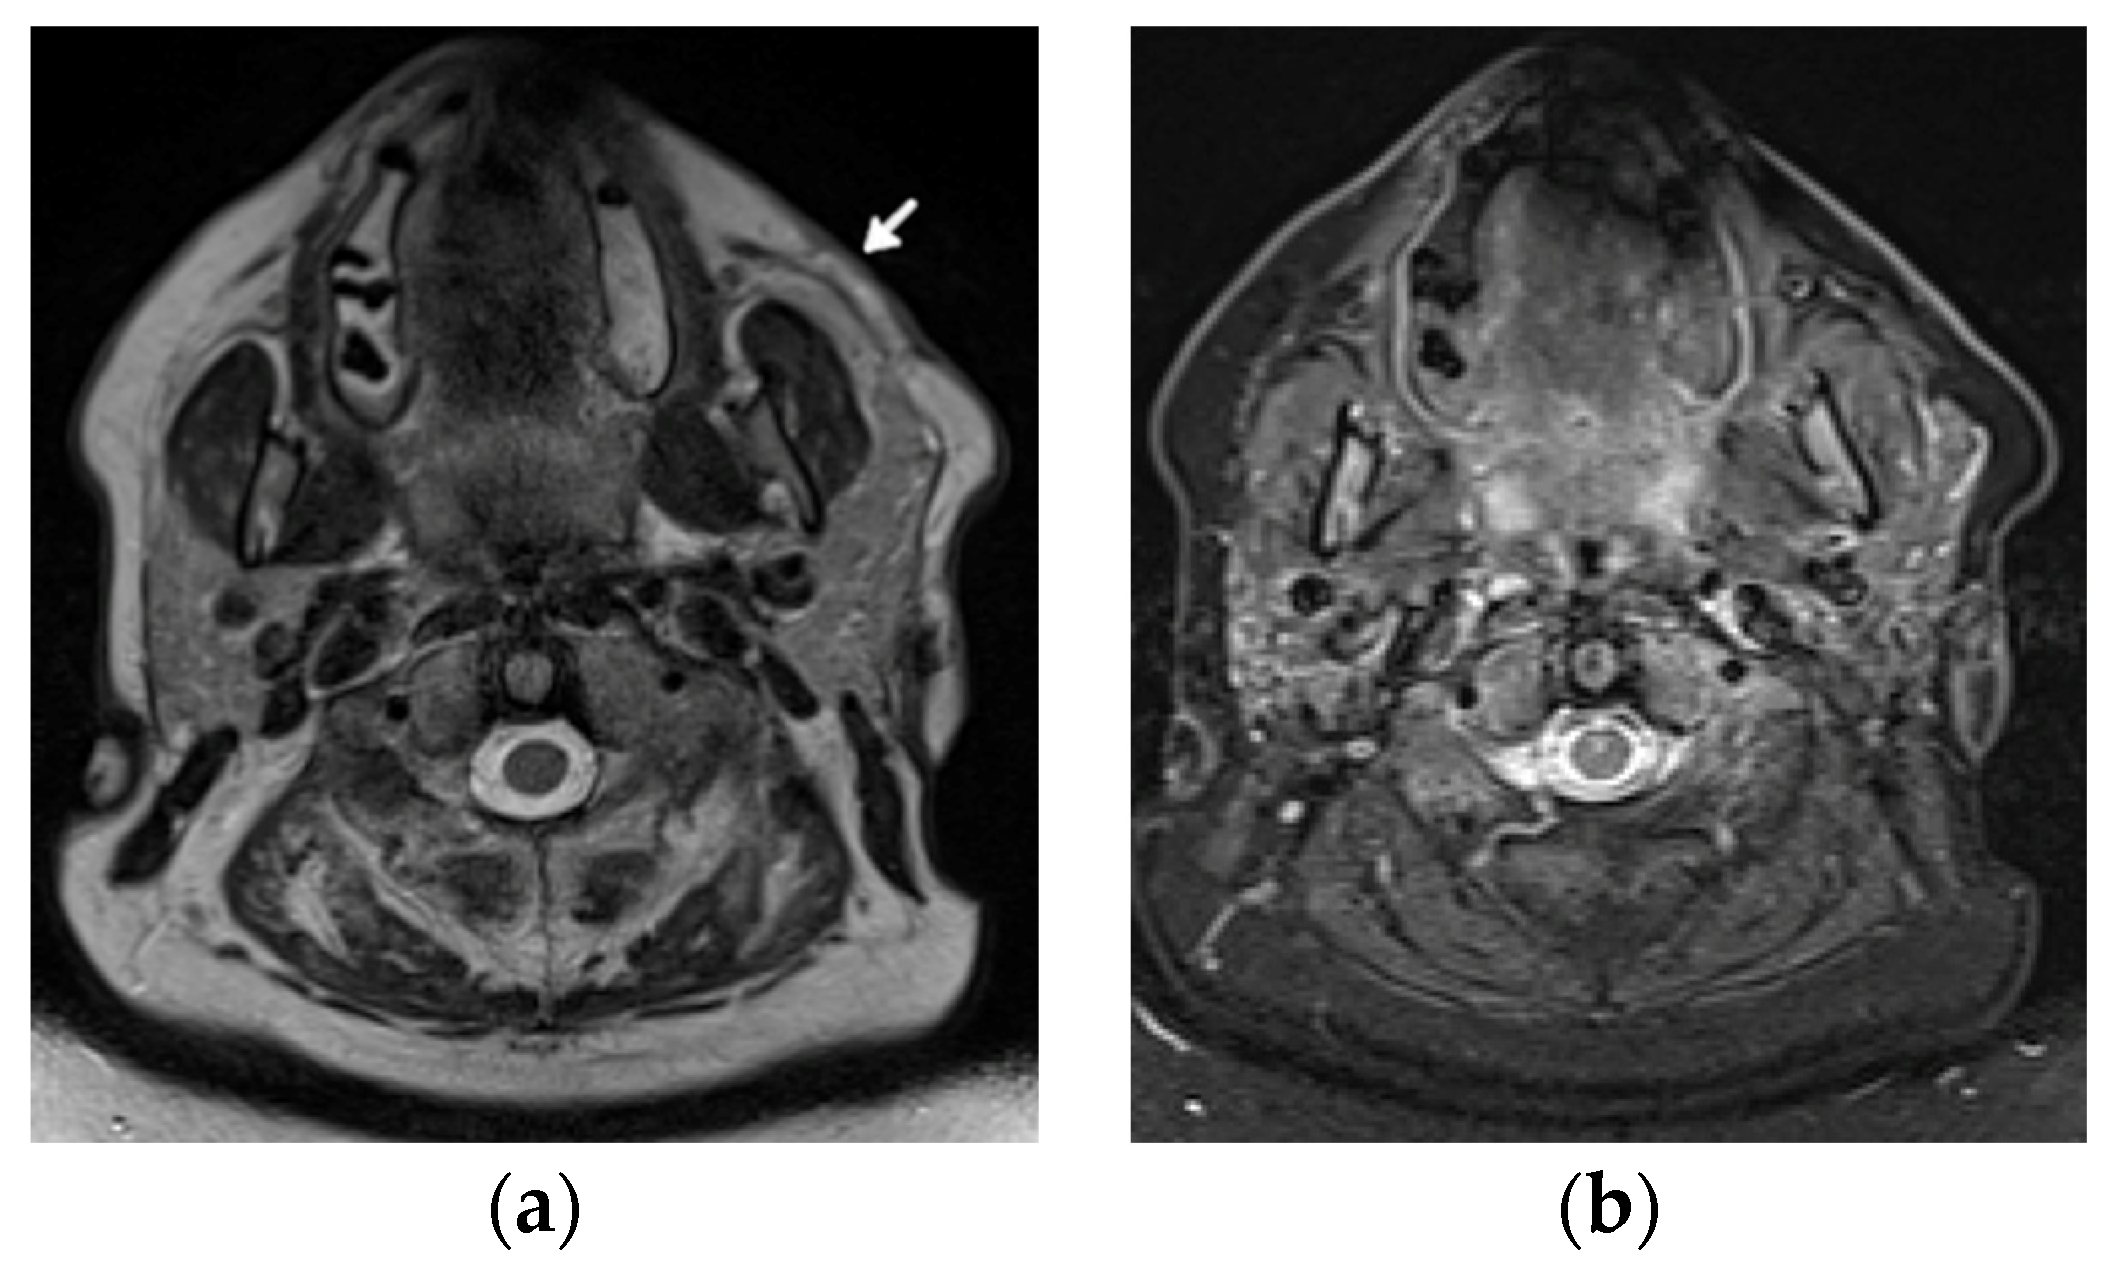

Diagnosis of ON and fractures is based on MRI in early stages (Figure 12) and radiography in advanced stages, like in adults.

Figure 12.

Magnetic resonance (MR) imaging of the femoral head osteonecrosis (ON) in a 14-year-old female with juvenile systemic lupus erythematosus. (a) Coronal and (b) axial proton density-weighted with fat saturation (right) MR images of the pelvis and right hip show a geographic serpiginous lesion in the right femoral head, with a bone marrow edema irregular contour and demarcation line consistent with ON (arrow).